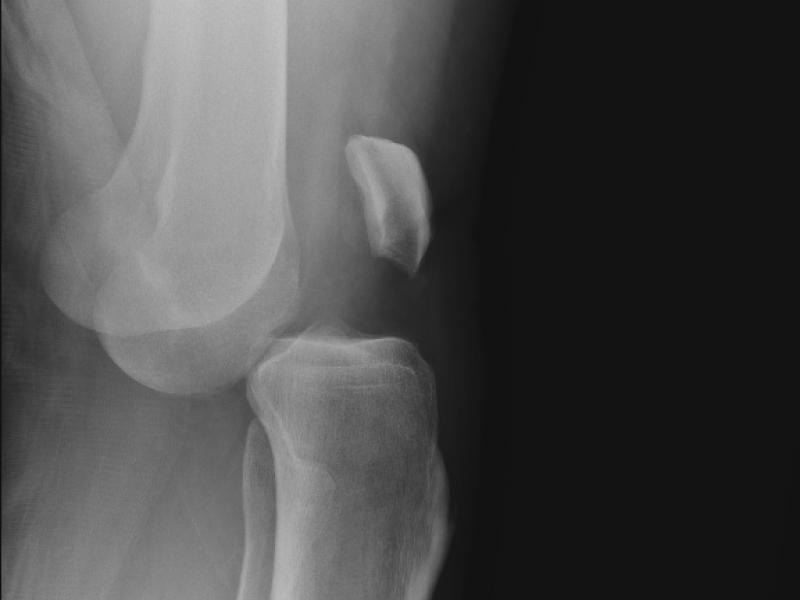

What's the diagnosis?  By Dr. Angela Ugorets

April 01 2020

A 26 yo male presents to the ED with severe left leg pain